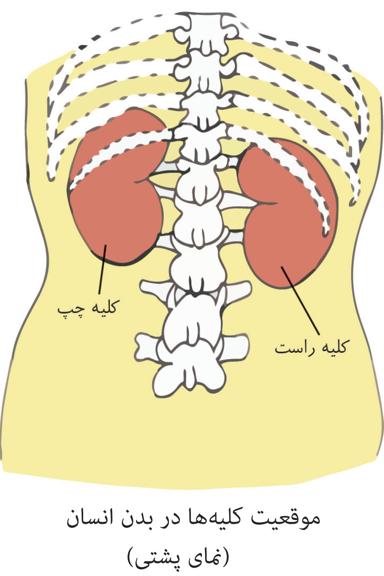

کلیهها، اندامهایی لوبیایی شکلاند و به تعداد دو عدد در طرفین ستون مهرهها و پشت محوطۀ شکمی قرار دارند. اندازۀ کلیه در فرد بالغ، تقریباً به اندازۀ مشت بستۀ اوست. به علت موقعیت قرارگیری و شکل کبد، کلیۀ راست قدری پایینتر از کلیه چپ واقع است.

هر دو کلیه در سطح زیرین دیافراگم قرار دارند.

سطح پایین هر دو کلیه توسط دندهها محافظت نمیشود.

دندههایی که از کلیه محافظت میکنند به استخوان جناغ اتصال ندارد، اما به ستون مهره مفصل شدهاند.

دندهها ازبخشی از کلیه محافظت میکنند. علاوه بر این، پردهای از جنس بافت پیوندی به نام کپسول کلیه، هر کلیه را در بر گرفته است.